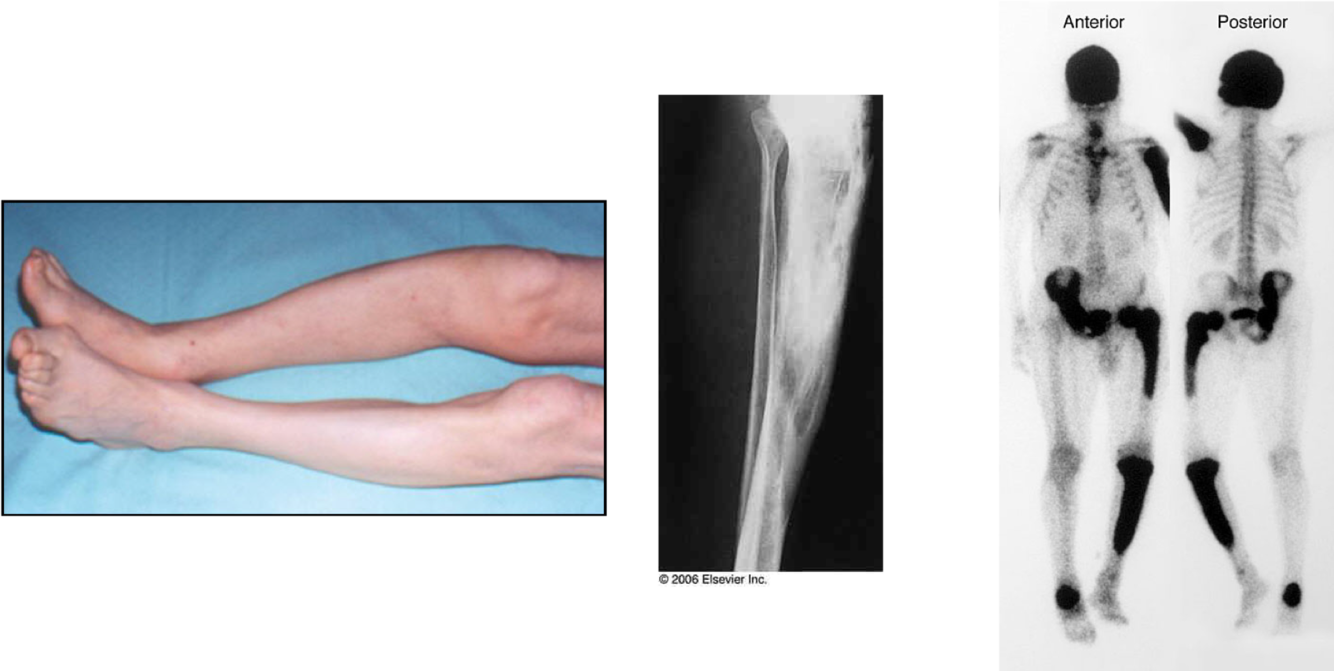

Paget’s Disease of Bone

what is pagets disease of bone?

Localised disorder of bone turnover

Increased bone resorption followed by increased bone formation

Leads to disorganised bone: bigger, less compact, more vascular and more susceptible to deformity and fracture

Paget’s disease of bone interferes with your body’s normal recycling process, in which new bone tissue gradually replaces old bone tissue. Over time, the disease can cause affected bones to become fragile and misshapen. Paget’s disease of bone most commonly occurs in the pelvis, skull, spine and legs

what are the symptoms of pagets disease?

presents in a patient >40 years with bone pain occasionally presents with bone deformity, excessive heat over the Pagetic bone or by neurological complications such as nerve deafness

Always over 40 and normally over 60

Constant deep seated bone pain

Long bones, forearm bones, also pelvis and skull but can be any bone in the skeleton

what is the presentation of pagets disease?

Isolated elevation of serum alkaline phosphatase (on blood analysis) - is the commonest presentation in the 21st centuary

Bone pain and local heat

Bone deformity or fracture

Hearing loss

Rarely the development of osteosarcoma in affected bone